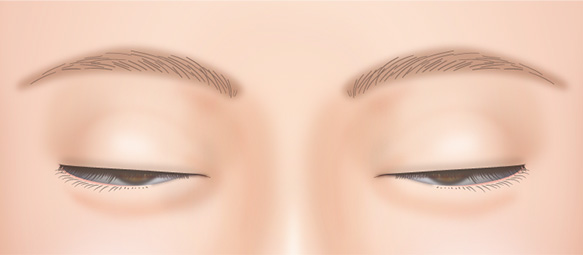

二重まぶた・目もとの修正手術は、前回の手術を受けてから最低6ヶ月以上空けてから行うことをおすすめします。

手術を受けてから6ヶ月の間は、腫れが引かず、完全な状態であるといえません。

この状態では正確なデザインをすることが難しく、どのような仕上がりになるのか予想がつきにくいからです。

また、瘢痕が未熟であったり、肥厚していたりするため、仕上がりが悪くなる可能性もあります。

無理に幅広の二重を作った場合、腫れが半年以上も続き、ハム目のようになる場合があります。

前回の手術で皮膚を大きく切除していていなければ幅の狭い二重に修正することが可能です。